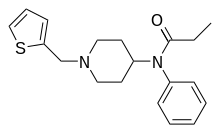

Anilidopiperidines

- 3-Allylfentanyl

- 3-Methylfentanyl

- 3-Methylthiofentanyl

- 4-Phenylfentanyl

- Alfentanil

- α-Methylacetylfentanyl

- α-Methylfentanyl

- α-Methylthiofentanyl

- Benzylfentanyl

- β-hydroxyfentanyl

- β-hydroxythiofentanyl

- β-Methylfentanyl

- Brifentanil

- Butyrfentanyl

- Carfentanil

- Fentanyl

- Lofentanil

- N-Methylcarfentanil

- Mirfentanil

- Ocfentanil

- Ohmefentanyl

- Parafluorofentanyl

- Phenaridine

- R-30490

- Remifentanil

- Sufentanil

- Thenylfentanyl

- Thiofentanyl

- Trefentanil

Structures